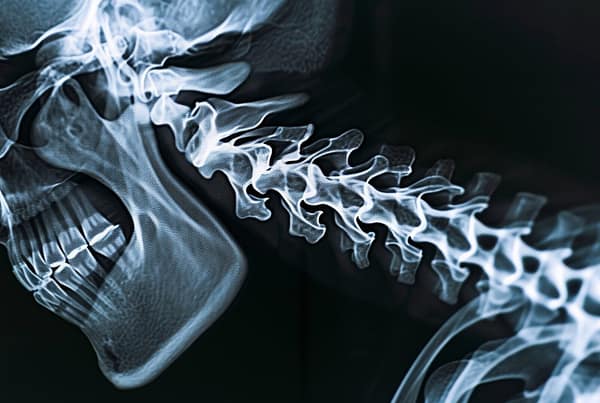

- Lesiones medulares: Dependiendo de la gravedad de la lesión, pueden provocar parálisis.

- Fracturas óseas: Piernas, brazos, pelvis y costillas suelen verse afectados en los accidentes de peatones.

Los accidentes de peatones pueden gama de lesionesdesde esguinces leves hasta lesiones graves de la médula espinal. El cuidado quiropráctico ofrece un enfoque holístico para tratar estas lesiones, centrándose en restaurar su alineación natural del cuerpo y función.

- Tratamiento del dolor: Los quiroprácticos se especializan en el tratamiento del dolor musculoesquelético, incluido el volver, cuelloy los arcenes, comúnmente afectados en los accidentes de peatones.